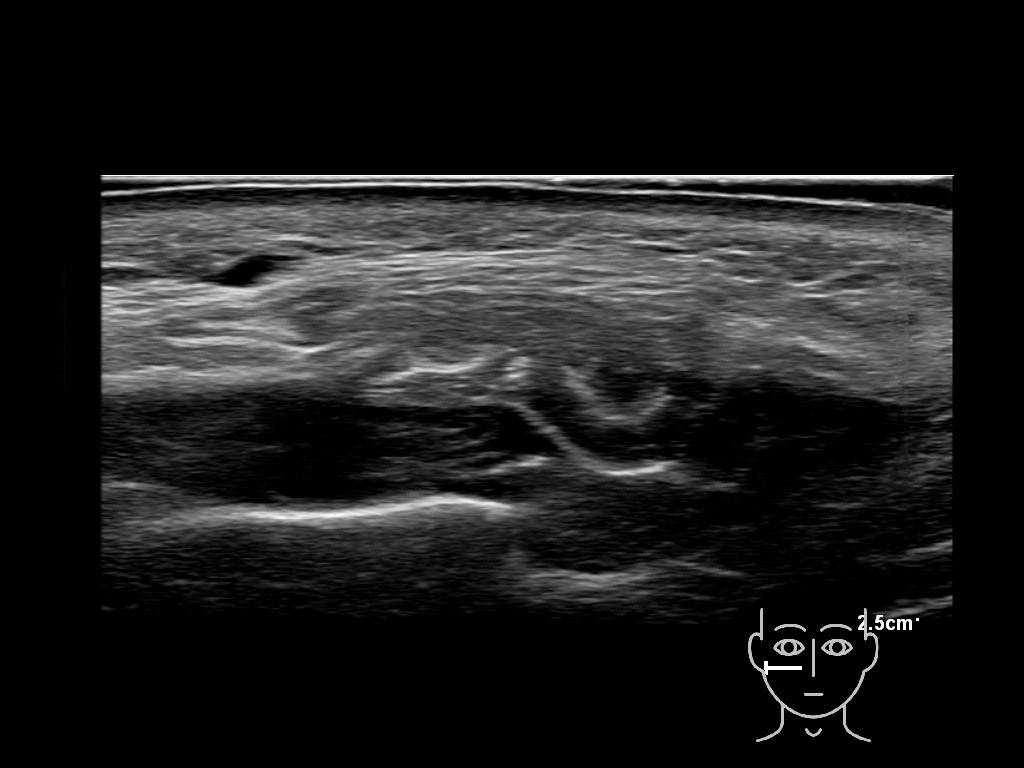

Fascia

Filler deposits may end up unintentionally in the SMAS or fascial layers of the skin. Very often this will not lead to adverse events, however, adverse events ( nodules, migration / redistribution impaired muscle movement and smiling and malar edema) are are often related to filler ending up in the SMAS or fascia.

Hover over an image to view the secondary image or click on the image title for more information.